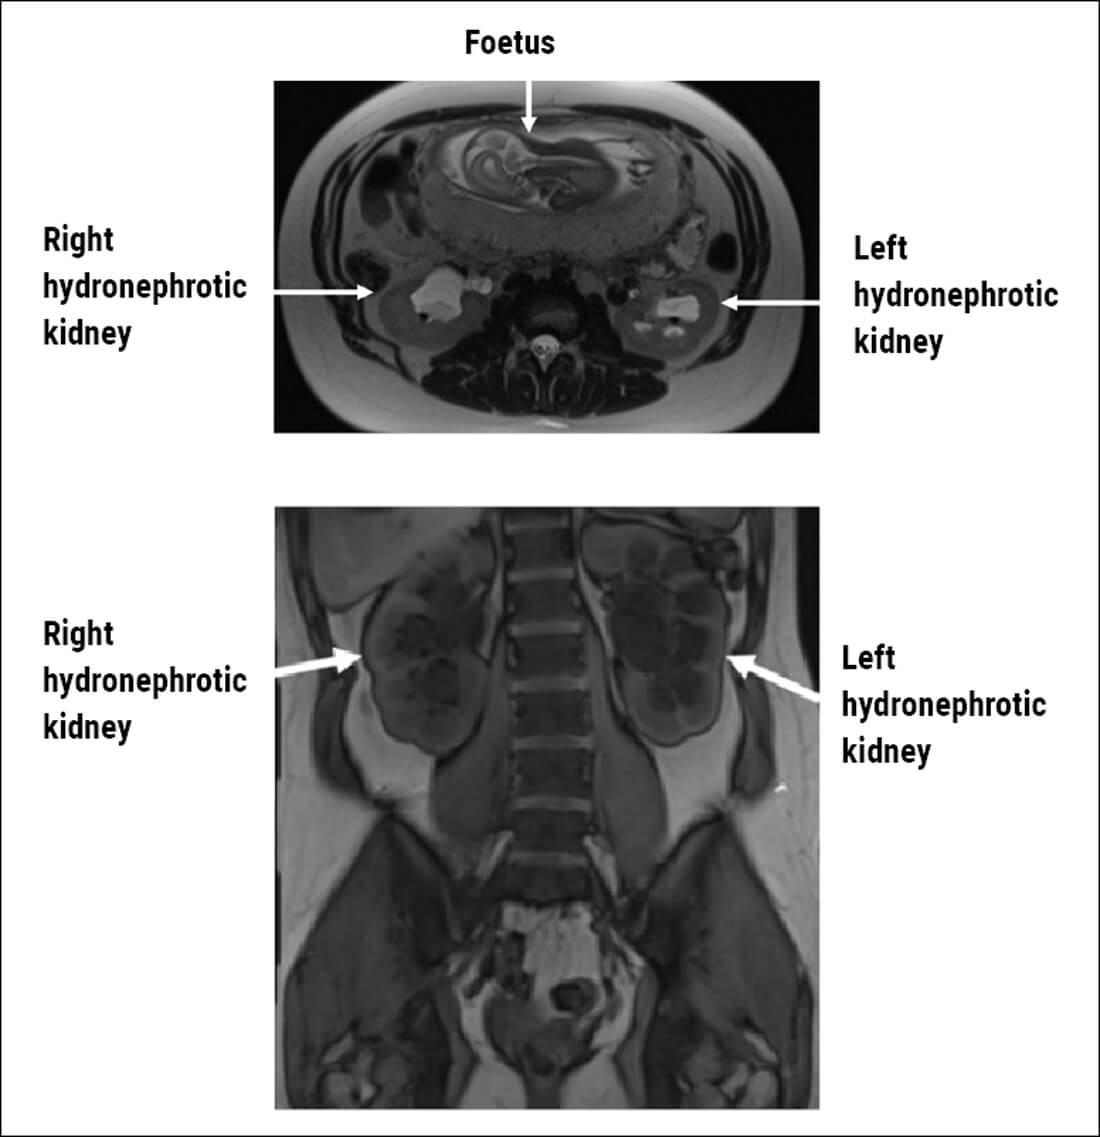

Figure 1: MRI scan in axial and coronal planes showing bilateral hydronephrosis in pregnancy.

- Ultrasound is the best first-line option as it is widely available and does not involve radiation. However, it has low sensitivity for renal and ureteric calculi. An additional option is MRI (Figure 1). MRI is expensive, and less readily available. MRI has increased accuracy when compared with US. MRI can show hydronephrosis and occasionally filling defects. There are no known risks from US or MRI during any trimester, but the use of contrast agents such as Gadolinium should be avoided. Ionising radiation should in general be avoided if possible. With the evolution of ultra-low dose CT, there is an option for diagnostic certainty with very little risk of radiation dosing to the foetus, but this is typically reserved for patients in whom surgical interventions are being planned as CT will lead to fewer negative ureteroscopies, and therefore reduce the anaesthetic risk to mother and foetus.